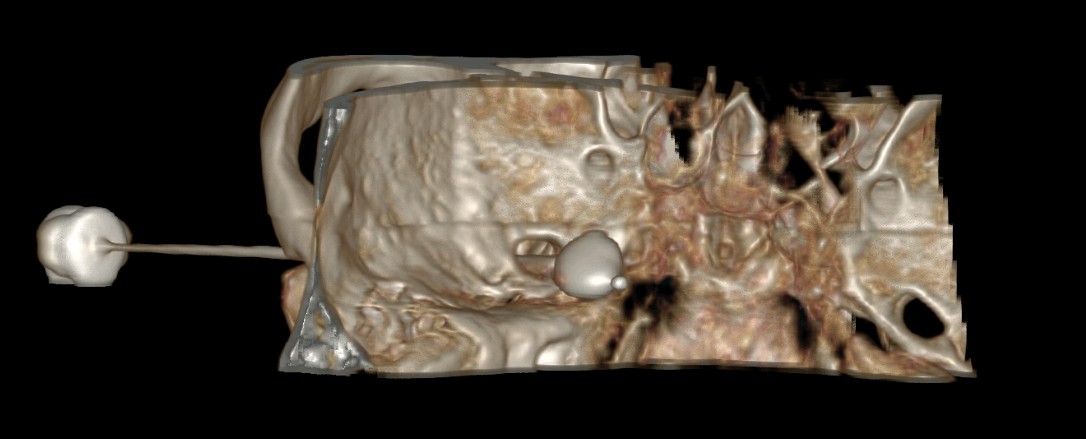

根据疼痛部位和疼痛的特点,结合三叉神经MRTA检查,王先生被诊断为三叉神经痛(V1)。一开始药物治疗有效果,疼痛有所缓解,但是一段时间后药物也不能控制疼痛了,王先生被收住入院。